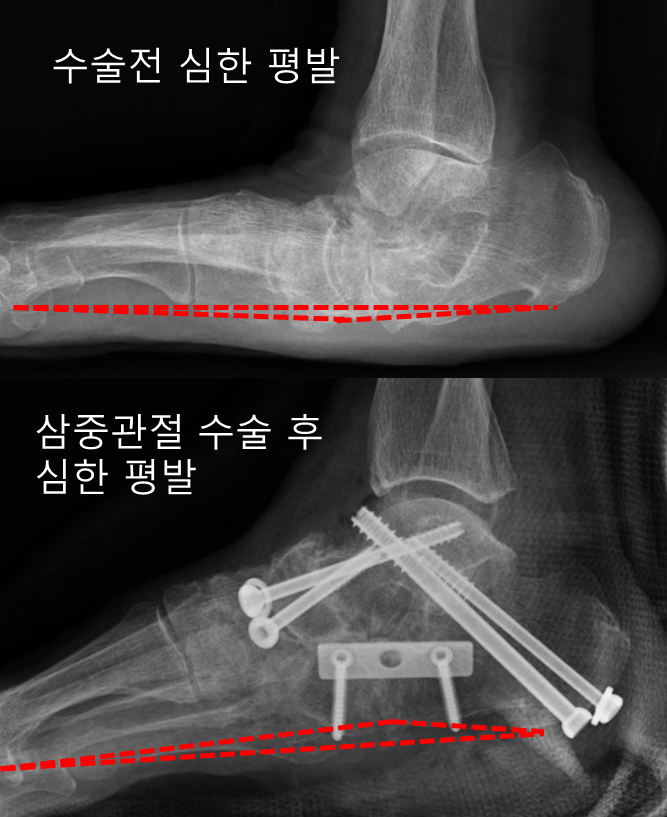

“평발은 치료가 필요없다.” 그것도 사실…..치료가 필요없다고…위 사진 보시면..다 평발로 인해 척추가 굽은 아이들입니다. 이러한 구부러진 척추를 교정하기 위해서는 평발 치료가 필요합니다. 아이들 평발을 무시한다면… 척추의 만곡도이니 무시하지 마시고, 무엇보다 조기발견과 조기치료가 중요합니다. 아이들이 다른 병원에서 평발 수술이 필요하다는 말을 듣고 엄마들이 “평발 수술을 해야 하는데…원해요?” 평발은 척추가 많이 휘어져 있습니다. 그런데… 평발 수술을 하면 이 척추가 좋아질까요? 척추는 여전히 구부러져 있습니다. 그렇다면… 척추는 재치료가 필요하고 평발 수술 없이도 아이들의 보조기는 수술의 부작용 없이 평발의 추가 발달을 예방할 수 있으며 일석이조로 세 마리의 새를 죽일 수 있습니다. 척추. 지난해 14세 학생이 평발 수술을 받고 병원을 찾았다. 아이의 걸음걸이가 정말 이상해서 어머니께 아이에게 장애가 있느냐고 물었습니다. 몇 년간 대학병원에서 평발을 관찰하다.. 결국 평발 수술을 받았는데.. 그런데.. 수술 후 아이는 정상적으로 걸을 수 없다고 한다. . 그래서 그는 이 걸음걸이를 고칠 수 있는지 알아보러 왔습니다. . 결론은 치료법이 없다는 것입니다. 평생 가는 것 같습니다. 집에서 평발을 정확하게 진단하세요. 1. 아이가 발을 어깨너비로 벌리고 서게 하세요. 2. 어머니는 아이 뒤에 쪼그리고 앉았다. 삼. 아이의 발목이 아래 그림처럼 안쪽으로 기울어져 있으면 평발입니다. 이 발이 보이면 병원에서 선 자세로 척추 엑스레이가 필요합니다. 저희 병원에서는 평발 치료에 30분에서 1시간 정도 소요됩니다. 아이의 발부터 척추까지 자세한 설명을 부모님께 드립니다. 자세히 설명하겠습니다. 이것은 다른 병원에서 일반적으로 수행됩니다. 확인 후 정상입니다. 발만. 나이가 들수록 좋아집니다. .